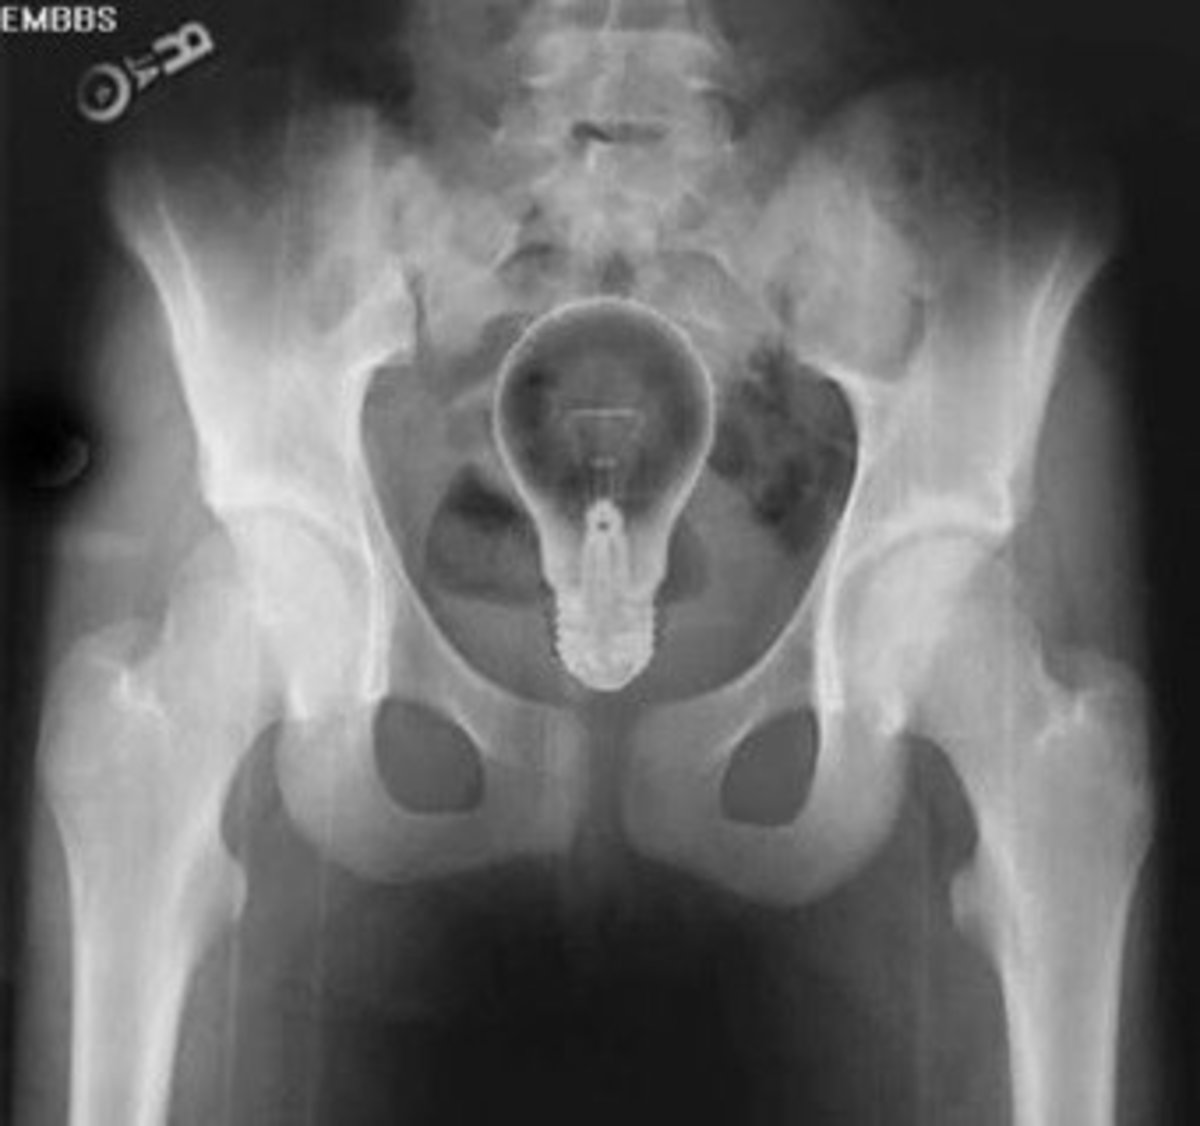

Light Bulb In Anus X Ray . Fecal impaction is most commonly a complication of chronic or severe constipation where inspissated hard feces accumulates in. Following the examination, the doctor. Ct scans should be reserved for those with potential sepsis or equivocal. If possible, they should be removed via the anus, although in some cases a laparotomy may be required. Obviously, if the object is very fragile for example, a light bulb, the proctoscope will be performed with a great deal of care, if it is done at all. Modern reports describe a cornucopia of objects resulting in retained rectal foreign bodies including vegetables, bottles, light bulbs, sex toys, a propane tank, and a billie club. Today, retained rectal foreign bodies remain a persistent chief complaint, with some evidence of an increasing incidence (11,16). A vibrator in the rectum.

Either this guy has a lightbulb up his ass or his Colon has a good idea r/Scrubs Light Bulb In Anus X Ray If possible, they should be removed via the anus, although in some cases a laparotomy may be required. Obviously, if the object is very fragile for example, a light bulb, the proctoscope will be performed with a great deal of care, if it is done at all. Modern reports describe a cornucopia of objects resulting in retained rectal foreign bodies. Light Bulb In Anus X Ray.

Doctors remove light bulb from man's anus Archyde Light Bulb In Anus X Ray Following the examination, the doctor. Fecal impaction is most commonly a complication of chronic or severe constipation where inspissated hard feces accumulates in. Modern reports describe a cornucopia of objects resulting in retained rectal foreign bodies including vegetables, bottles, light bulbs, sex toys, a propane tank, and a billie club. If possible, they should be removed via the anus, although. Light Bulb In Anus X Ray.